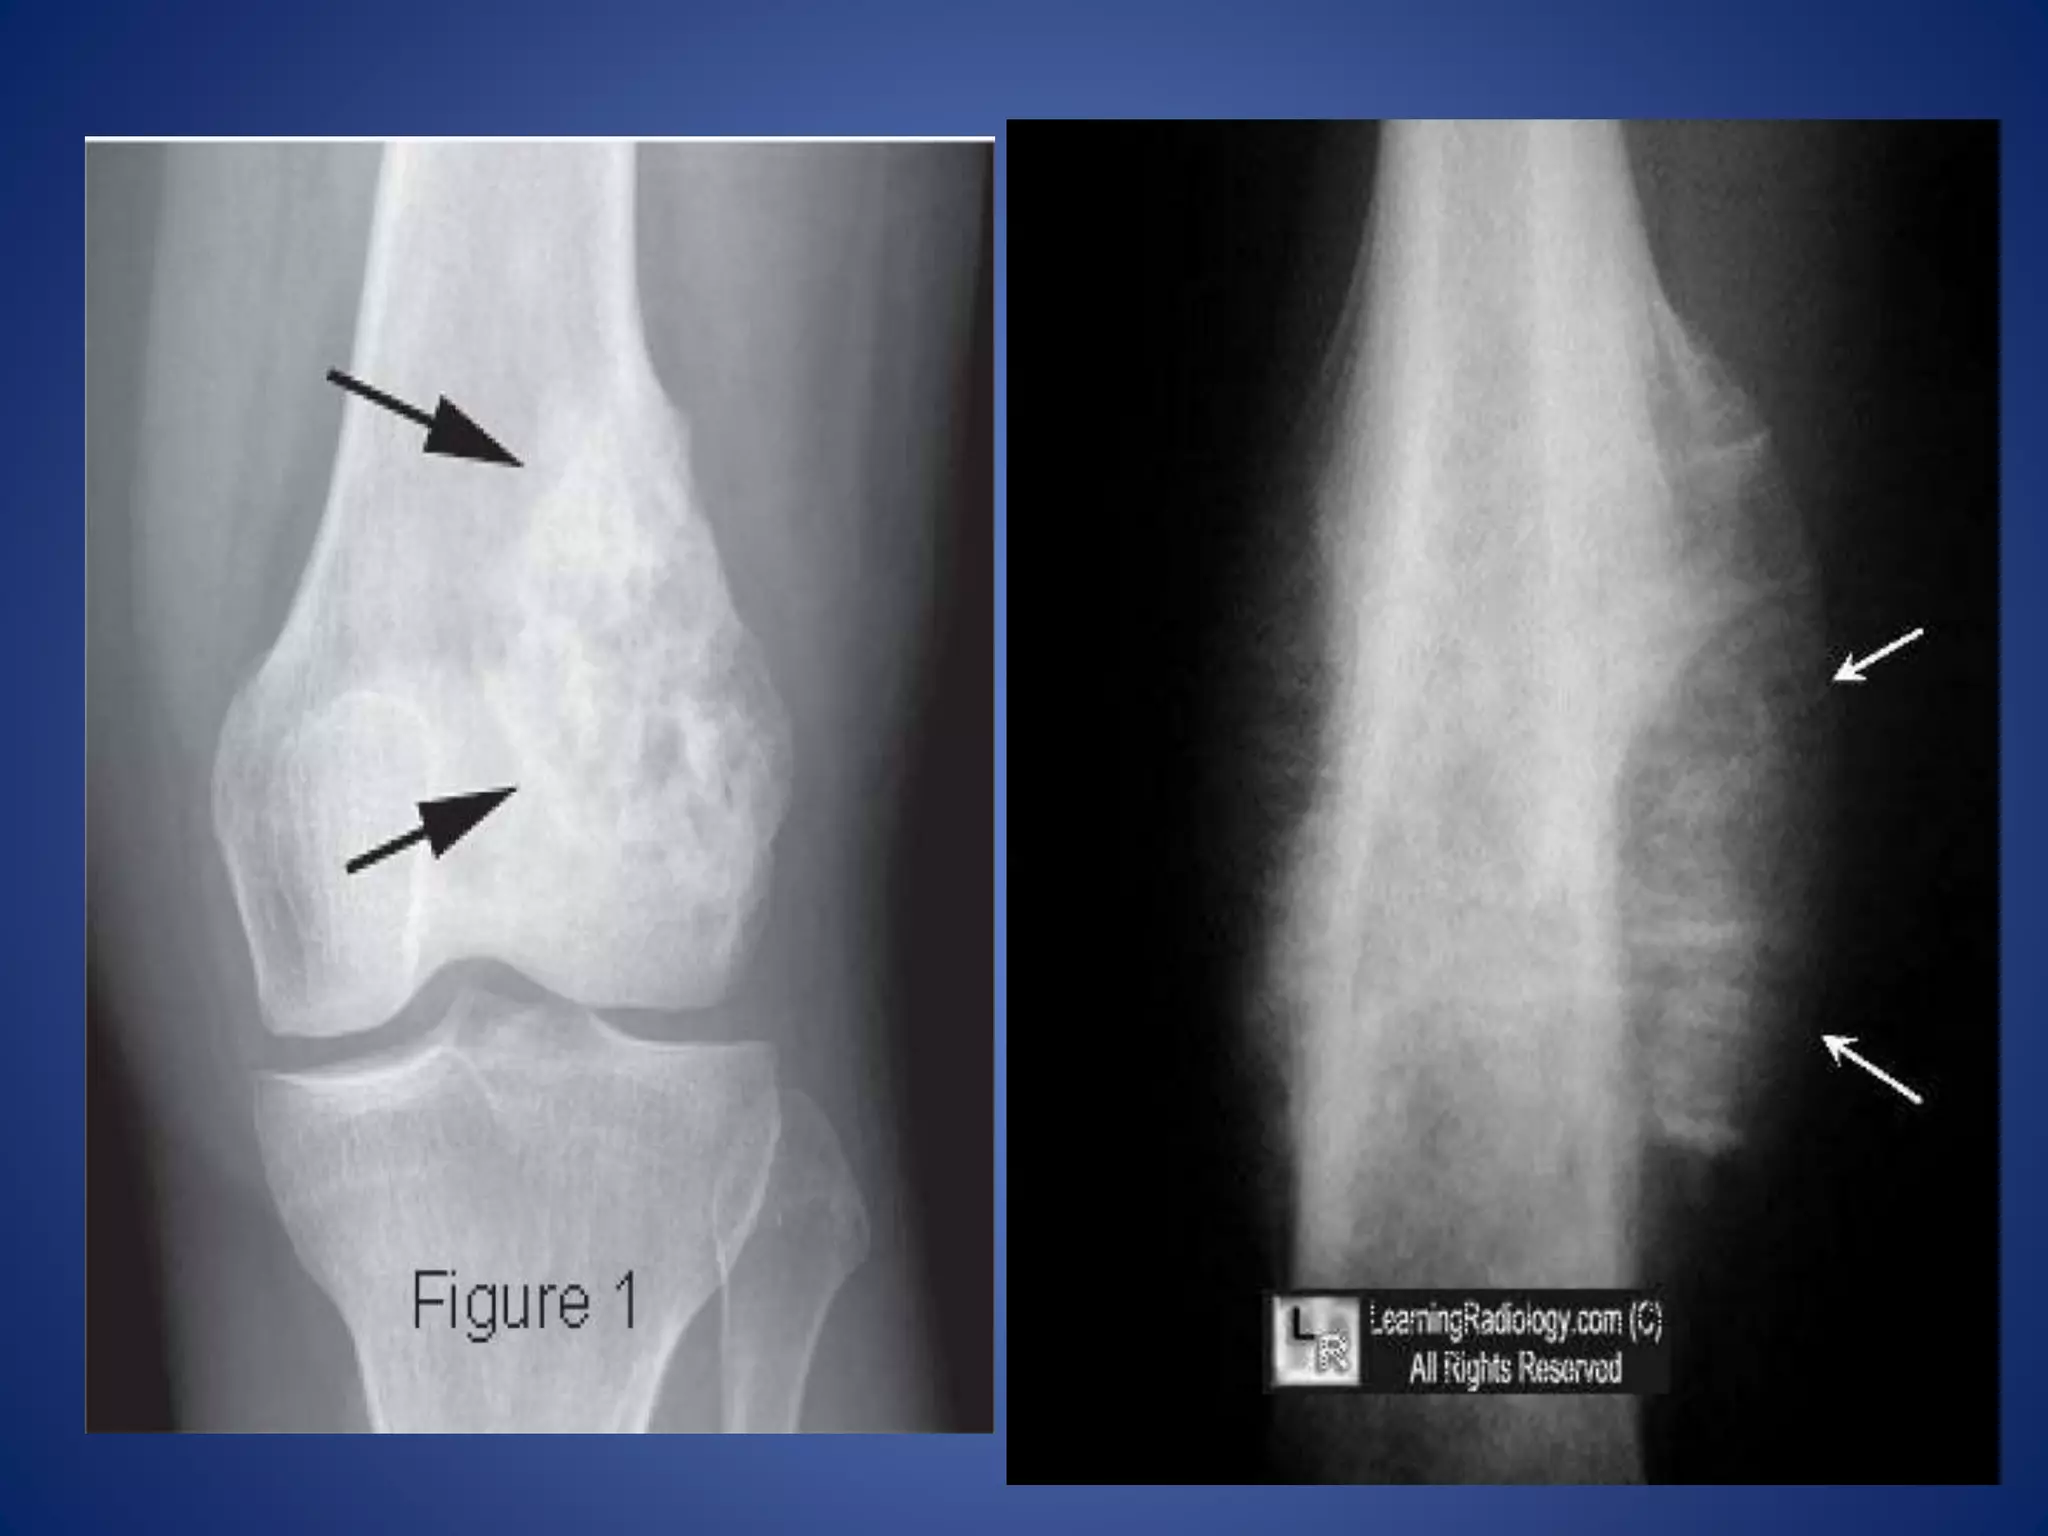

X-Ray findings

• Usually show an area of bone destruction which,

unlike osteosarcoma, is predominantly in the mid-

diaphysis.

• New bone formation may extend along the shaft and

sometimes appears as fusiform layers of bone

around the lesion – ‘onion-peel’ effect.

• Often the tumour extends into the surrounding

tissues, with radiating streaks of ossification and

reactive periosteal bone at the proximal and distal

margins.

• The ‘sunray’ appearance and Codman’s triangle.

Radiological Findings

 hazy osteolytic areas which may alternate with unusually dense

osteoblastic areas.

 Area of irregular destruction in metaphysis, sometimes

overshadowed by new bone formation

 Erosion of cortex overlying lesion

 There may be also a poorly define endosteal margin.

 Periosteal reaction : Tumor lifts the periosteum which is

irregular , smooth layer in OM

 Codman’s triangle: Reactive new bone formation at the angles

of periosteal elevation.

 Sun- ray appearance/Sunburst effect: Growing tumor grows into

the overlying soft tissues, bone laid down along blood vessels

within tumor growing centrifugally